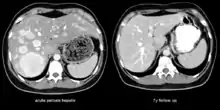

The CT scan of a patient with peliosis hepatis (left): The follow-up CT (right) after 7 years shows full remission. | |